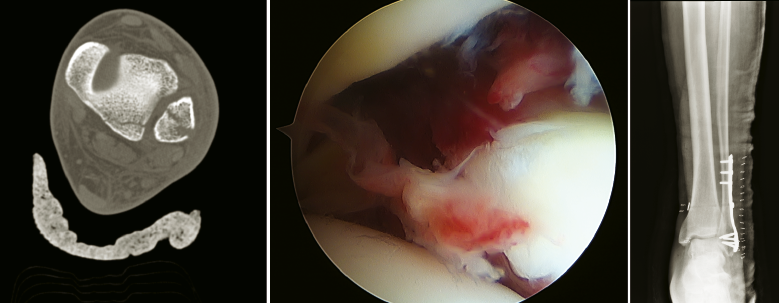

- Traumatología de pie y tobillo: fracturas complejas de tobillo, calcáneo, astrágalo y mediopié. Reducción abierta y osteosíntesis con asistencia artroscópica (Figura 8).

Figura 8. Fractura tobillo SER III. Asistencia artroscópica para valoración de sindesmosis.